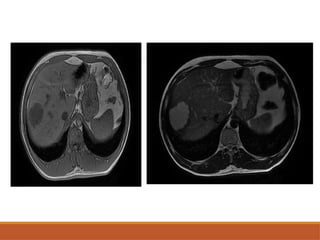

• #48 Axial plain image showing intrahepatic biliary radicular dilation and illdefine dhypodense lesion in segment 5 On cect in arterial phase the lesion is showing peripheral enhnacenet with retention of contrat in delayed phases IHBRD with retention of contrats in delayed phass indicates cholangiocarcinoma

• #50 Axial T1 nad T1 c images showing a illdefined T1 hypointense lesion in seg 4 and 5, 8 of liver with associated intrahepatic biliary radicular dilation The elsion is showing heterogenous contrast enhnacm,ent and retention of contsrt in delayed pahses